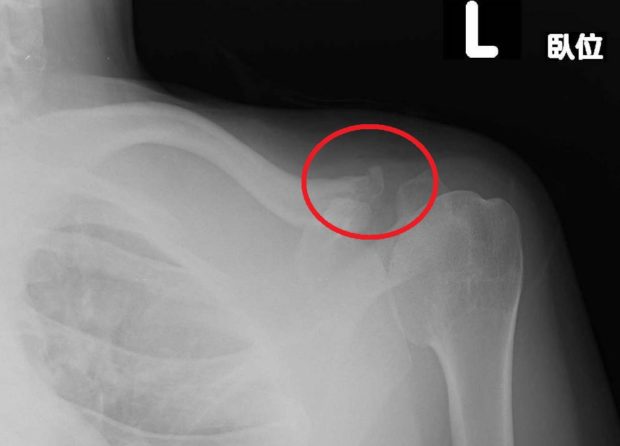

紹介をした整形外科で撮ってもらったレントゲンです。

赤丸で囲った部分に軽度の変形がみられます。

明らかな変形や強い痛みがなくても骨折をしている

ことがあるため、自己判断は厳禁です!!